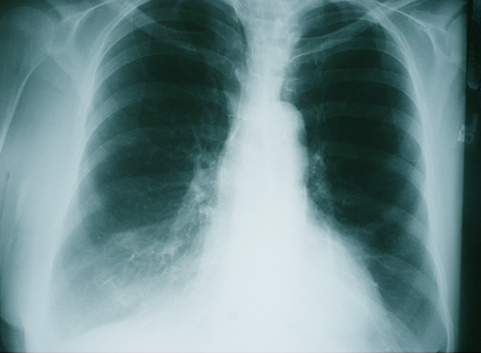

Innym badaniem wykorzystywanym do ustalenia rozpoznania jest badanie radiologiczne klatki piersiowej (RTG), w którym często nie stwierdza się istotnych zmian. Natomiast w przypadku występowania u chorego nasilonej rozedmy płuc (jedna ze składowych POChP), radiolog opisze pewne nieprawidłowości widoczne w badaniu. Do wykonania badania niezbędne jest skierowanie od lekarza (lekarza POZ, lekarza chorób płuc lub innego specjalisty) niezależnie od tego, czy jest wykonywane komercyjnie, czy jest finansowane przez NFZ.